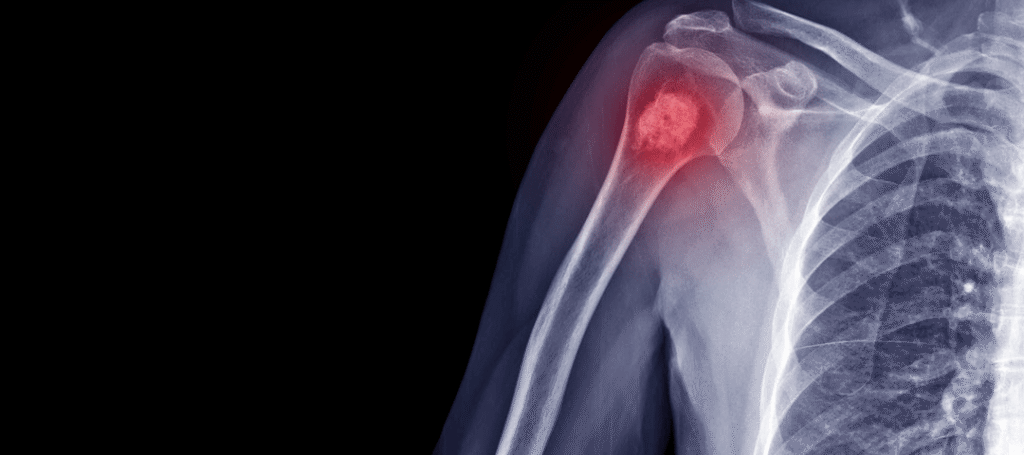

cancer-de-huesos

Ciudad de México.- El osteosarcoma es un tipo de cáncer óseo agresivo que suele afectar a niños y adolescentes, caracterizado por el crecimiento descontrolado de células óseas anormales. En este caso, la joven paciente fue diagnosticada con osteosarcoma con metástasis en pulmón, una condición que complica el tratamiento y reduce las opciones terapéuticas convencionales.